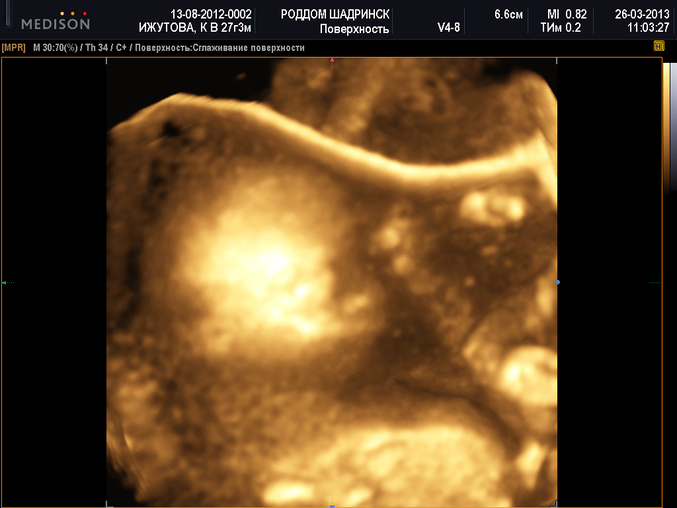

Это доча)))

УЗИ, КТГ, доплер, скрининг, ХГЧ и другие анализыДевочки всем спасибо за пожеланияВернулась с УЗИ! Слава Богу, с малявками всё хорошо. Два писюля на пол экрана - сыночки))) Один лежит поперёк (поперешный будет, в отца))). И сверху девочка лежит (тоже поперек - мояяя))), скромно прикрыв ручками лицо))) Всё все рассмотрели. Правда фото не отчетливые. Одну выбрала, для просмотра, та, что по-лучше)))